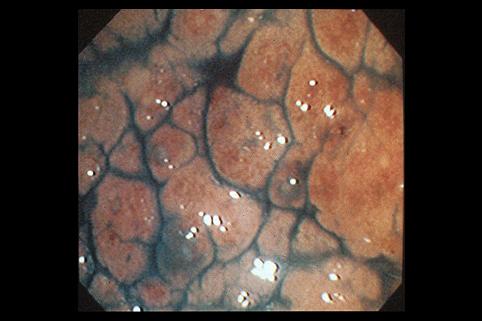

clasificación del pacienteTumor Epitelial Maligno/Adenocarcinoma

parte(separada por órganos)colon/lesión que abarca dos o más regiones del colon

método de exámenEndoscopia

clasificación ectoscópica de tumoresTipo 4(Tipo difusamente infiltrado)/

diámetro mayor del tumor40 -

grado de penetraciónss(a1)